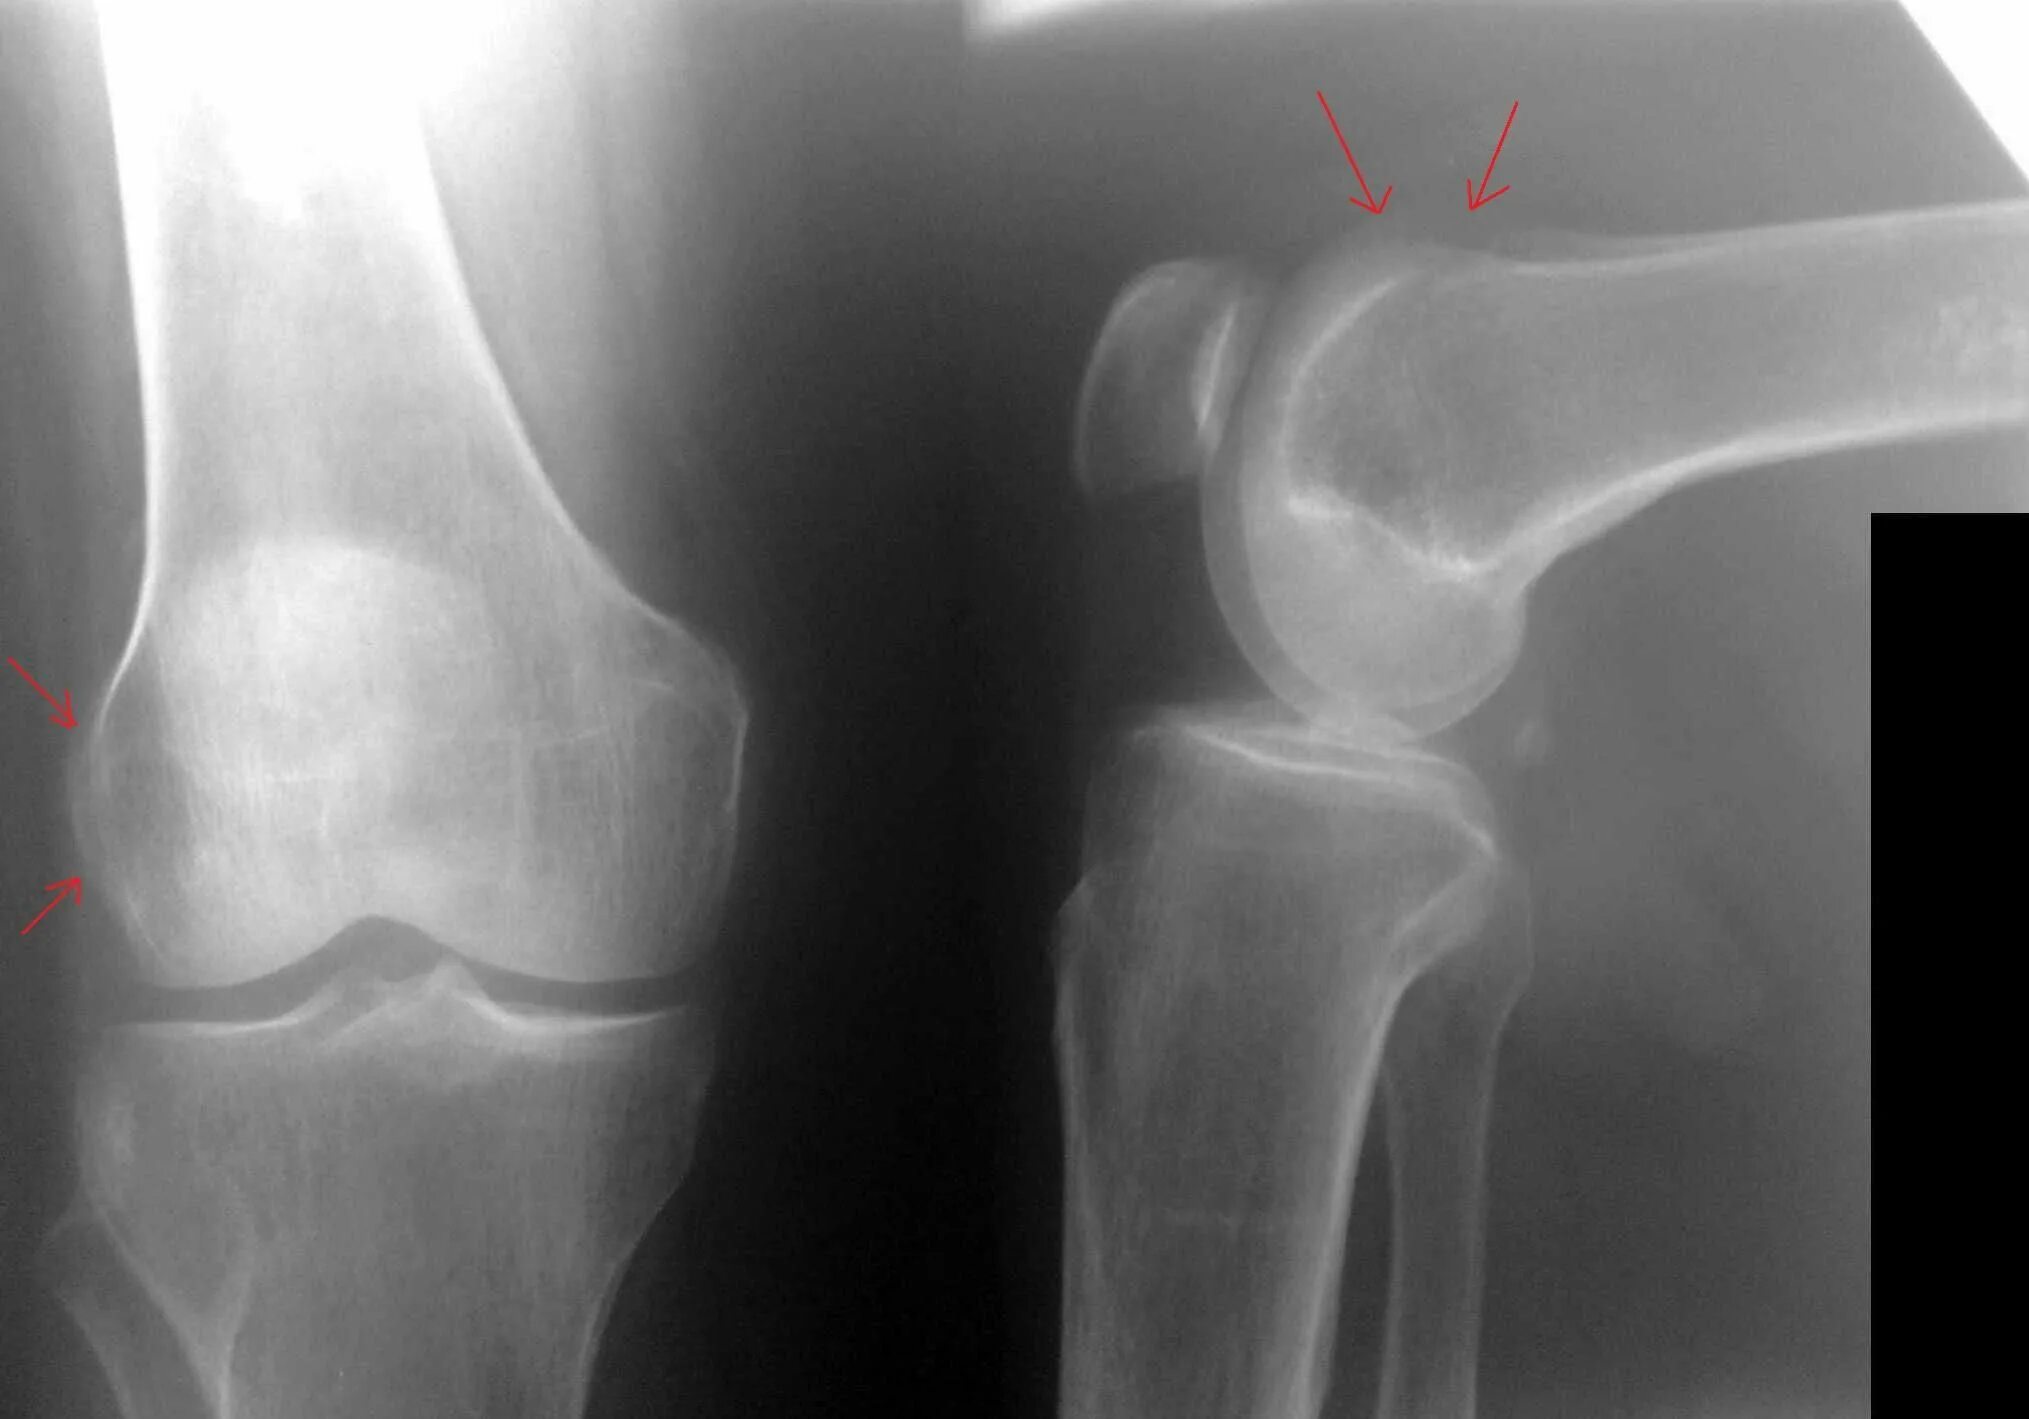

Деформирующий гонартроз коленных суставов 2 степени